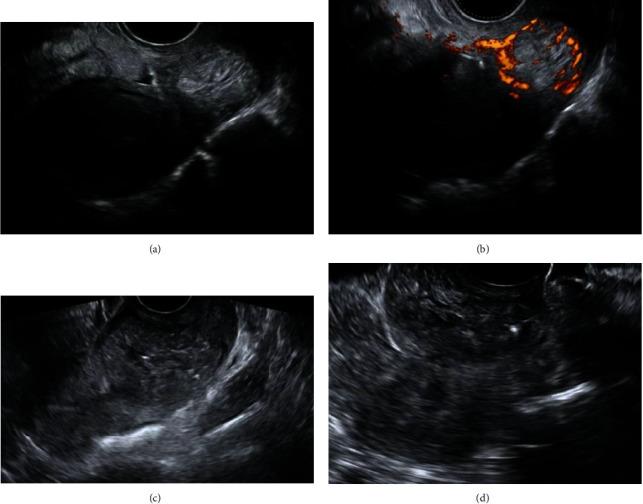

This study is aimed at describing a noninvasive conservative strategy to the treatment of cervical pregnancy and highlighting the success of ultrasound-guided therapeutic techniques. A 43-year-old woman with a history of one previous cesarean section presented in our unit with vaginal spotting and a positive urine pregnancy test. She was diagnosed with a cervical pregnancy, and she was successfully treated conservatively with the administration of intragestational sac methotrexate under ultrasound guidance. Cervical pregnancy is a rare form of ectopic pregnancy that results from conceptus implantation in the cervical canal. The main concern is the associated life-threatening hemorrhage and subsequent need for urgent hysterectomy. The evolution of ultrasound over the past decades has enabled early diagnosis and has shifted the management from a radical surgical approach towards a stepwise conservative therapeutic approach, when possible.

本研究旨在描述一种治疗宫颈妊娠的非侵入性保守策略,并强调超声引导治疗技术的成功。一名有一次剖宫产史的43岁女性因阴道点滴出血和尿妊娠试验阳性就诊于我院。她被诊断为宫颈妊娠,并在超声引导下通过向妊娠囊内注射甲氨蝶呤成功进行了保守治疗。宫颈妊娠是一种罕见的异位妊娠形式,由孕卵植入宫颈管引起。主要问题是可能出现危及生命的出血以及随后需要紧急子宫切除术。在过去几十年中,超声技术的发展使得早期诊断成为可能,并在可能的情况下将治疗方式从根治性手术方法转变为逐步保守治疗方法。